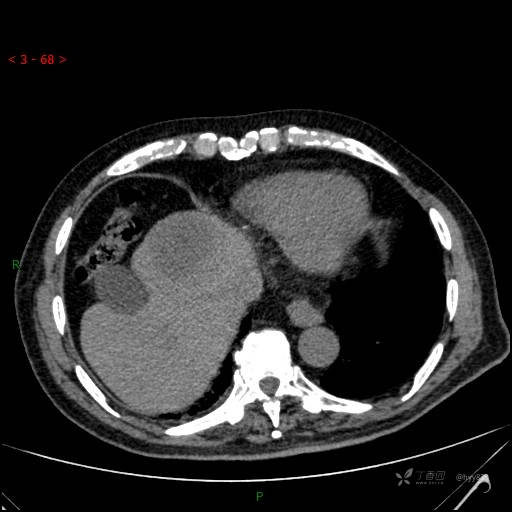

静脉期

img